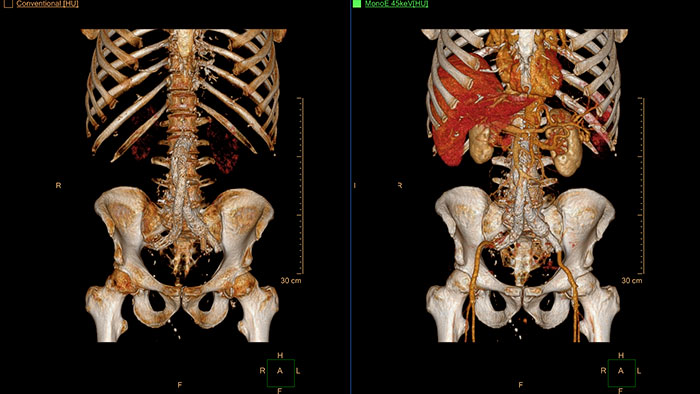

Spectral Advanced Vessel Analysis

CT Spectral Advanced Vessel Analysis

IQon Spectral CT Functionality

Benefits

• Bone removal on different energy levels.

• Spectral plots to characterize plaque and stenosis.

• Different energy results comparison.

• Evaluation of the extent of lumen occlusion.